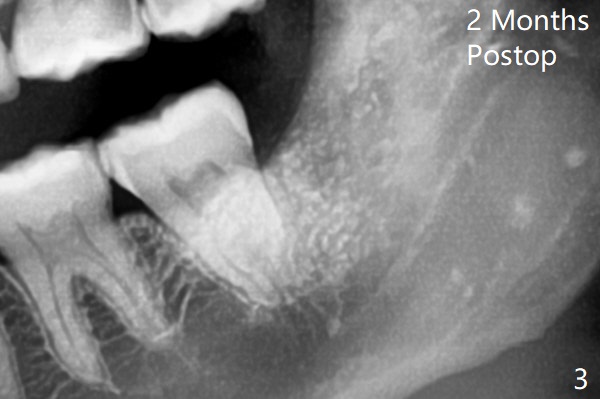

7和8之间只有一层骨皮质(图一:>),8拔除后(图一’),7远中骨质可能退缩,所以植骨尤其重要。医用石膏(Bond Apatite,图二),表面放置1/2胶原塞,4-0 PGA缝合。术后两个月回来拔除左上8(“刺激颊粘膜”,其实远中牙龈红肿),临床上左下8近中颊侧仍有一个小开口,石膏与骨质界限开始不清楚了(图三)。